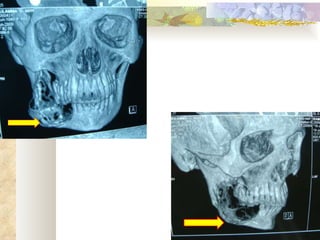

INVESTIGATIONS Radiological – OPG, lateral occlusal mandibular radiograph Complete blood picture, CT, BT Incisional biopsy

Bicortical expansion

RADIOLOGICAL FEATURES Unilocular radiolucency, especially early lesions that often progress to multilocular ( soap-bubble, honeycomb ) May be associated with impacted tooth Cortical expansion and thinning Resorption of adjacent tooth roots, displacement of teeth can be seen